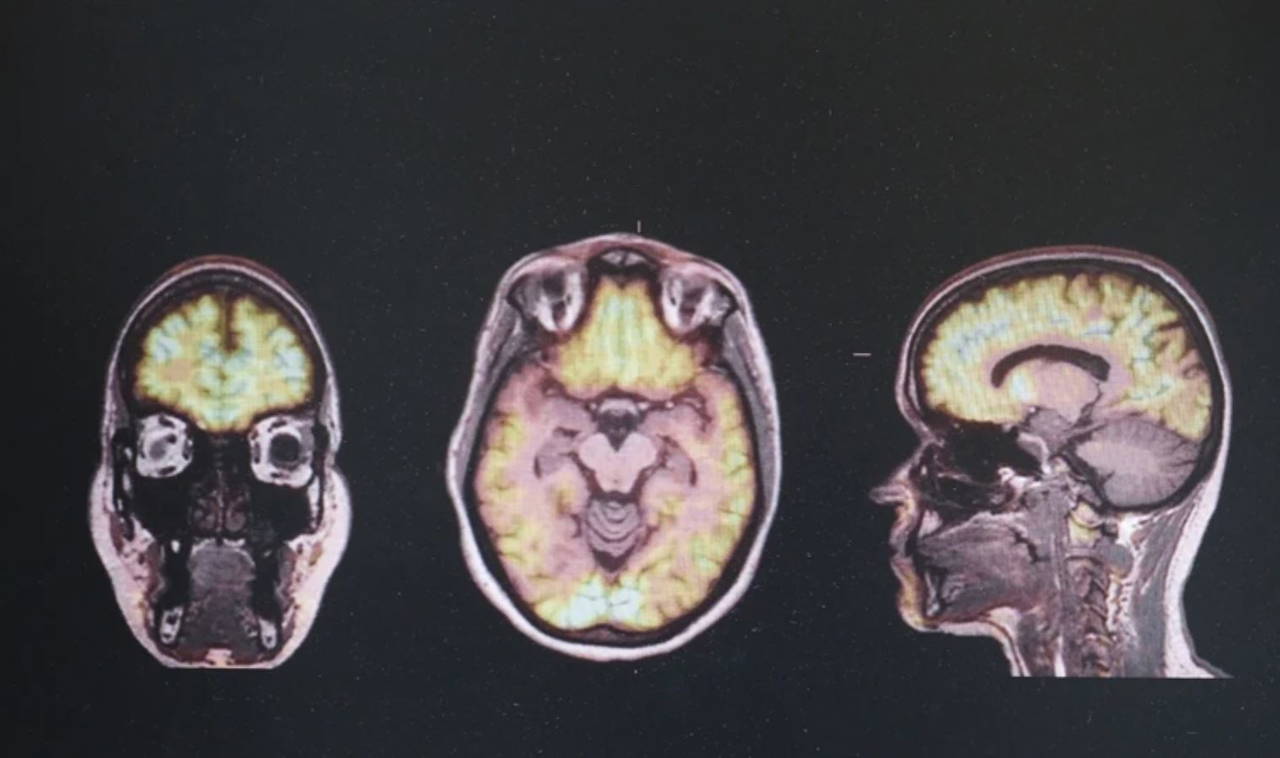

Yüksel, özellikle günümüzde kesin bir tedavisi bulunmayan nörodejeneratif hastalıklara ilgi duyduğunu ve kendini bu yönde geliştirmek için ekip arkadaşlarıyla çalışmalar yaptıklarını aktardı. Beyindeki nöron fonksiyonlarının ilerleyici kayıp ve yapısal bozulması olarak isimlendirilen nörodejeneratif bozukluklar içinde frontotemporal demans, Alzheimer, Parkinson, ALS, Huntington gibi hastalıkların yer aldığını anlatan Yüksel, bu hastalıkların dünya genelinde ciddi bir sağlık sorunu olduğundan, kendisinin de bu alana yönelik çalışmalar yaptığını dile getirdi.

"Ben de bu hastalıkların erken teşhisinde yapay zekadan yararlanabilir miyiz diye merak etmeye başladım. Sonrasında iki arkadaşımla takım olarak, farklı faktörlerin genlerin çalışması üzerindeki etkisi olarak adlandırılan epigenetik tabanlı bir yapay zeka modeli geliştirdik. Bu modeli, söz konusu nörodejeneratif hastalıkların erken teşhisinde kullanılması amacıyla geliştirdik. Beş hastalığa odaklandık. Bunlar, frontotemporal demans, Alzheimer, Parkinson, ALS, Huntington. Bu yapay zeka modeli 5 nörodejeneratif hastalığın epigenetik tabanlarını içeriyor."